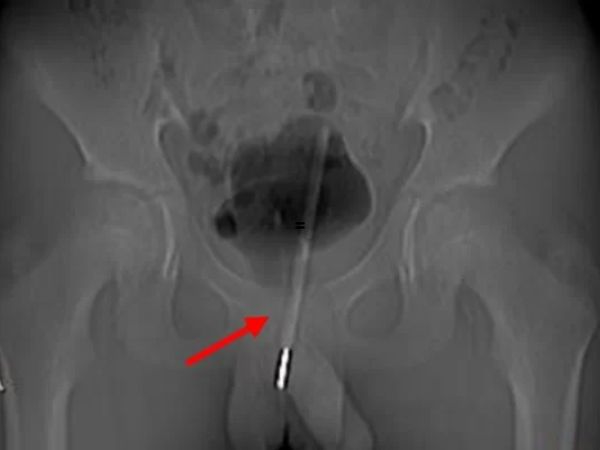

Adolescente passa por cirurgia após inserir termômetro no órgão genital (Foto: Chengdu First People's Hospital)Exames de raio-X mostraram que o termômetro chegou à bexiga do menino. Os médicos temiam que ele pudesse machucar outros órgãos se fosse retirado da mesma forma que entrou e optaram por uma cirurgia menos invasiva, com pequenas incisões, para retirá-lo pela bexiga. A operação foi bem-sucedida e sem sequelas para o paciente.